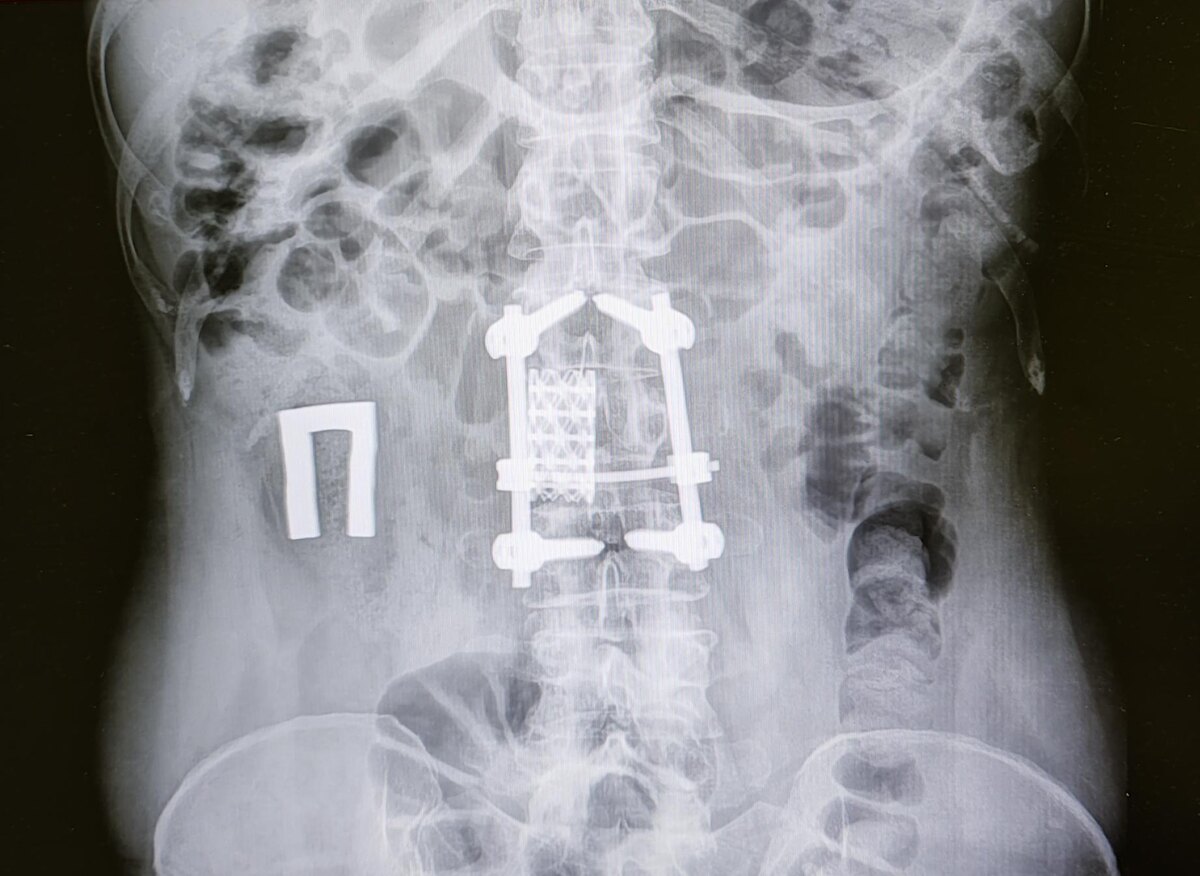

Оскольчатый перелом L2 позвонка, транспедикулярная фиксация с корпородезом MESH⁠⁠

В анамнезе оскольчатый перелом L2 позвонка, оперативное лечение.

Состояние после транспедикулярной фиксакции L1, L3 позвонков, люмботомия справа, с резекцией части тела L2 позвонка, передний корпородез MESH -по поводу травмы грудопоясничного отдела позвоночника с компрессионно-оскольчатым переломом L2 позвонка.

Категория годности по ст.81(Последствия переломов позвоночника, костей туловища, верхних и нижних конечностей (переломов костей таза, лопатки, ключицы, грудины, ребер, плечевой, лучевой и локтевой костей, шейки бедра и бедренной кости, большеберцовой и малоберцовой костей, надколенника и других костей): а)последствия переломов, в том числе травматическая спондилопатия (болезнь Кюммеля), вывихов и переломовывихов тел позвонков после хирургического лечения с применением спондило- и корпородеза- Д(не годен к военной службе) по I, II, III графам.